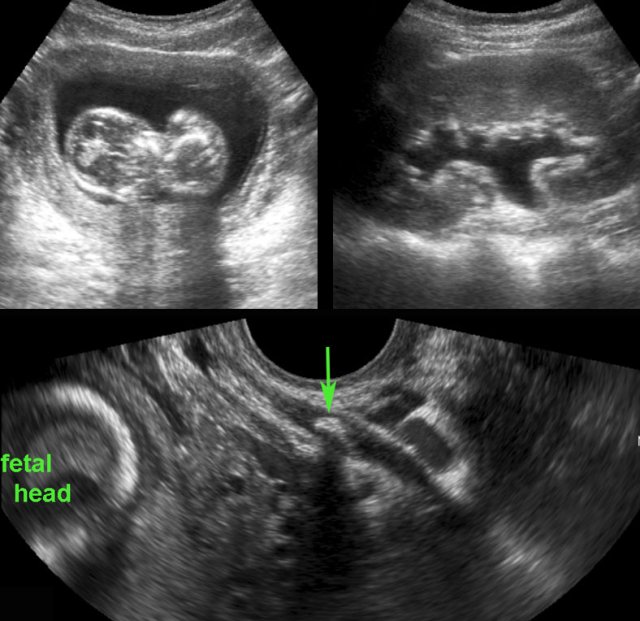

Uncomplicated course of sigmoid diverticulitis documented by TVUS. Uncomplicated course of sigmoid diverticulitis documented by TVUS.

Diverticulitis

A 34-year old woman, presented with acute LLQ pain.

TVUS demonstrated local wall thickening of the sigmoid and a diverticulum harbouring a fecolith (arrow), which was surrounded by inflamed fat (*), representing mesentery and omentum, effectively walling-off the imminent perforation.

The next day, she felt much better and follow up TVUS showed a hypoechoic, oedematously thickened, empty diverticulum (arrowhead).

The fecolith apparently did evacuate to the sigmoid lumen.